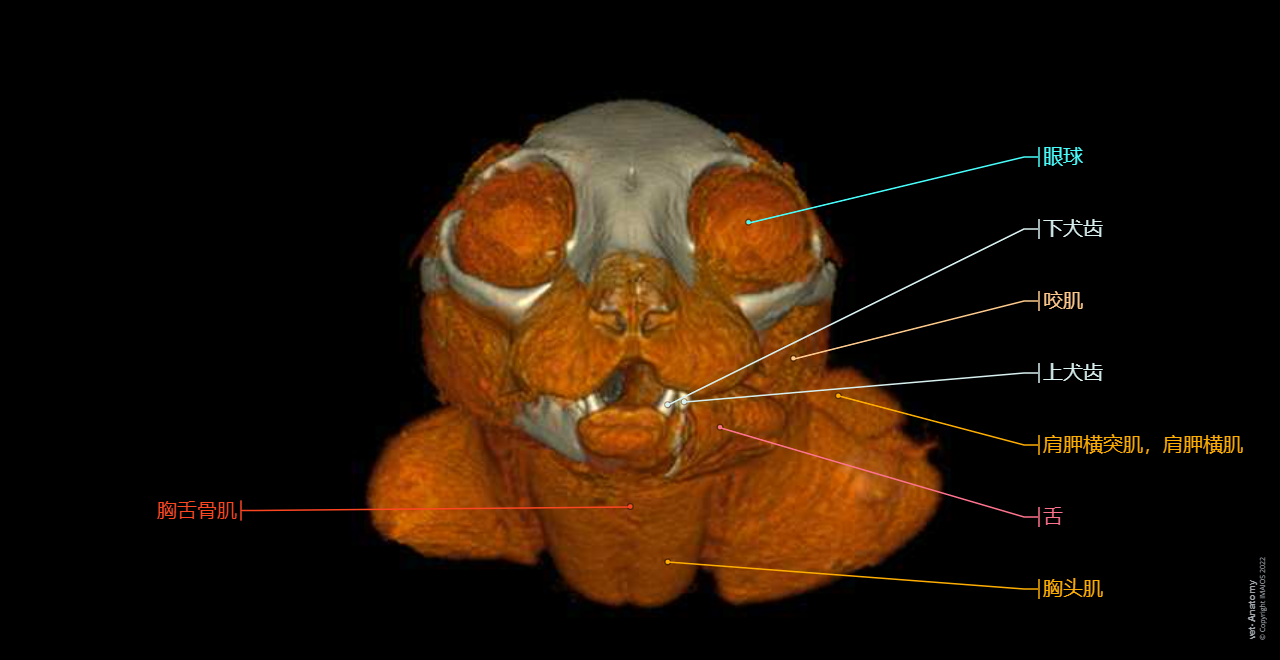

正常猫的头颈部CT解剖

- Antoine MICHEAU, MD , Denis HOA, MD , Susanne AEB Boroffka, PhD - dipl. ECVDI

- 发布日期: 2019年10月11日 | 最新更新 2025年3月18日